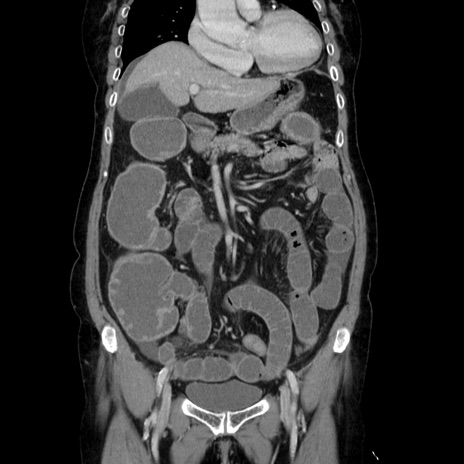

症例5(冠状断像)

【症例】70歳代女性

【主訴】お腹が張る

【現病歴】1週間くらい前から腹部膨満の自覚あり。昨日夜から増悪したため、本日救急外来受診。

【身体所見】意識清明、BT 36.5℃、BP 165/106mmHg、HR 80bpm、SpO2 98%、腹部:膨満、軟、自発痛・圧痛なし、触診にて不快感あり、腸蠕動音:減弱

【データ】WBC 12600、CRP 1.04